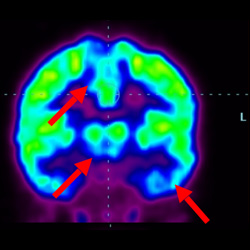

細胞治療前 PET CT 掃描顯示神經組織中的藍/黑色區域,表明腦癱引起的大腦損傷。

細胞治療后,藍色和黑色區域減少,并且看到更活躍的區域。這表明損傷減少并改善了大腦功能。

這證明細胞療法是治療腦癱兒童安全有效的方法。細胞療法可以更新大腦損傷的核心,并且可以通過 PET CT 掃描來監測大腦的改善情況。這些細胞療法與標準治療一起促進腦癱兒童的生長和改善。